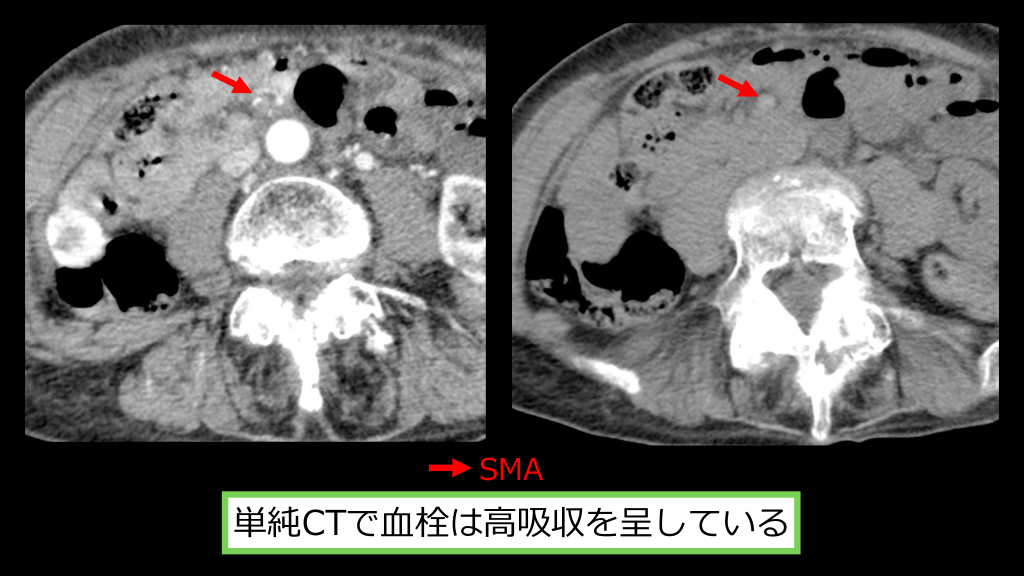

SMA 単純CTで⾎栓は⾼吸収を呈している

回盲部、⼩腸の壁の造影効果は減弱している